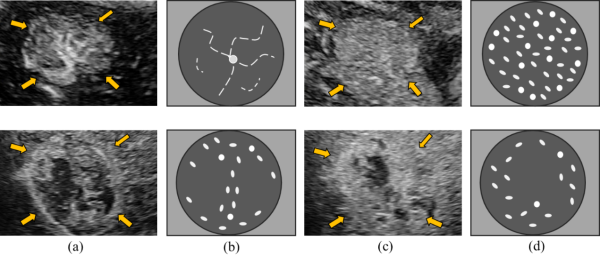

(1)提出实现首个关注非典型肝癌(图20)领域的计算机辅助诊断算法。

(2)提出基于诊断语义的时空域特征提取算法(图21),用于Contrast-Enhanced Ultrasound (CEUS) 的视频帧分析。

相关数据代码下载

图20.非典型肝癌与良性肿瘤之间的图像语义差异, 上列为良性肿瘤,下列为非典型肝癌。(a) 动脉相肿瘤区域 (b) 轮辐状(上列)与混乱状(下列)。(c) 延迟相肿瘤区域 (d) 均匀增强 (上列)与不均匀增强(下列)

图21.提出的Spatio-Temporal Semantics算法模型。